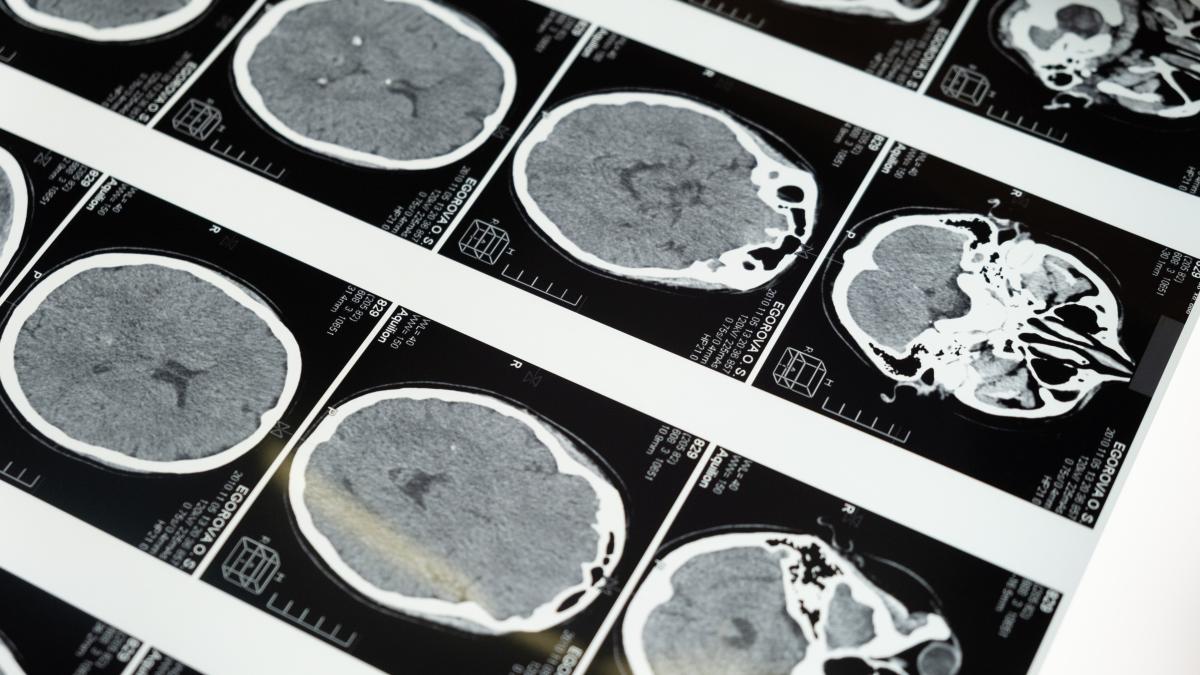

Prof.dr. Vlad Ciurea, neurochirurg la Spitalul Clinic Sanador, a fost întrebat dacă este diferit creierul unui intelectual față de cel al unui om de rând.

„Este foarte dificil de răspuns la așa ceva. Pot să spun, însă, din operațiile pe care le-am făcut, că cel mai degradat creier este cel al alcoolicului. Este un semn mare de alarmă, pentru că este un creier ratatinat, se stafidește”, a spus Vlad Ciurea, medic neurochirurg și director științific la Spitalul Clinic SANADOR.